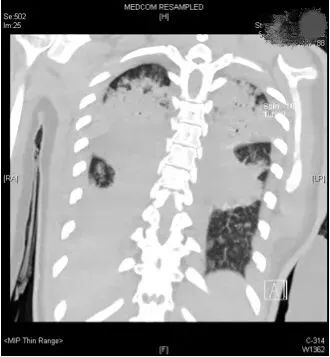

评估结果不容乐观,呼吸机的支持水平要求很高,100%纯氧条件下小文体内的氧分压才勉强达标,持续高烧超过40摄氏度,CT复查提示两肺几乎全部实变,炎症指标非常高。

(小文的影像检查显示,双肺几乎完全实变)